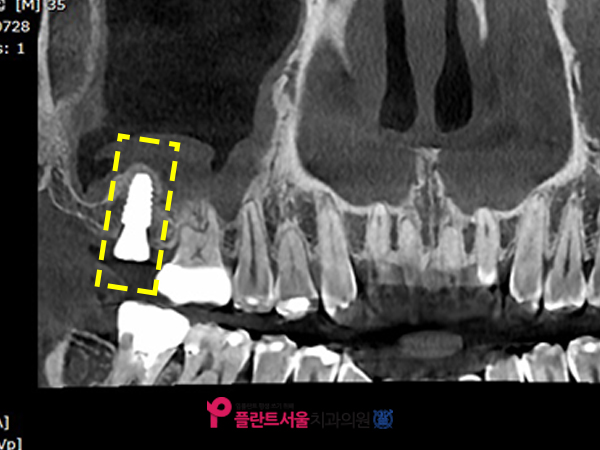

저희 병원에 처음 내원하셨을 때 찍었던 X선 사진입니다. 1년 전 위턱 제2대 어금니(#17)를 발치한 뒤 다시 이곳에 인공 치아를 심기 위해 오포치과 플랜트 서울에 오셨습니다. 환자분의 경우 꽤 오랜 기간 동안 치아가 없는 상태로 지내 왔습니다만. 이와 같이 발치 후에 장기간 그대로 두면 주위 치아가 빈 공간으로 기울어지거나 마주보는 아랫니가 위로 뻗어나와 보철을 심을 공간이 부족할 수 있으며 발치 후에는 가능한 한 빨리 인공치아를 심는 것이 좋습니다.

환자의 경우 다행히 옆에 #16번 치아가 밑에 있는 #47번 치아와 맞물려서 잘 잡고 있어서 부품을 심을 수 있는 충분한 공간이 있었습니다. 본 병원은 보다 정확한 검사를 위해 대학 병원급의 3DCT를 사용하여 환자의 구강 상태를 파악했습니다.

CT사진

노란색으로 표시된 부분은 인공치아를 심을 때 뼈를 이식하는 상악동입니다. 반대쪽과 비교했을 때 뭔가 꽉 차있는 게 보이죠? 콧물이나 고름, 점액질을 비롯한 각종 이물질들이었어요.

코 막힘이나 콧물이 나오고 있는 증상이 있다고 말씀을 하셨는데. 앞서 말씀드렸듯이 축농증으로 인해 비어 있어야 할 공간에 이물질이 가득 차게 되면 상악동을 들어올리는 과정에서 천공이 발생할 수 있으며, 공간 확보가 제대로 되지 않아 픽스처를 식립하기가 어려울 수 있습니다.

인공치근 주변에서 2mm 이상의 뼈를 만들어야 하는데, 이렇게 내부에 쌓여있는 이물질의 압력으로 인해 안전하게 식립이 어려운 것이죠. 만약 해당 부위에 무리하게 인공치아를 심을 경우 천공 이외에도 나중에 보철치가 흔들리거나 탈락될 수 있고 여러 합병증이 발생할 수 있으므로 본원은 가장 먼저 축농증을 완화시킨 후 골이식 임플란트를 진행하는 치료계획을 수립하였습니다.